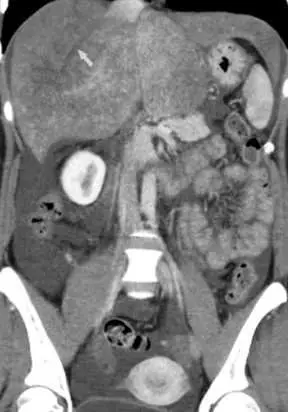

下圖為巴德–吉亞利症候群(Budd-Chiari syndrome)病人的肝臟電腦斷層影像,此疾病是指 肝臟何種結構發生阻塞?

Budd–Chiari syndrome 為肝臟靜脈迴流受阻所造成的綜合徵。主要病理在於肝靜脈(hepatic vein)或其近端至下腔靜脈(inferior vena cava)段發生血栓或機械性阻塞,造成肝臟無法有效將血液排出,導致肝臟淤血、腫大、門脈高壓及腹水等臨床表徵。

從本題提供之腹部對比強化電腦斷層影像可見:

- 肝臟實質呈現不均質、高低密度混雜的「馬賽克樣(mosaic)增強」分布,反映肝臟局部灌流差異,為血流阻塞後典型表現。

- 頂端箭頭處可見預期應被含氧血填充的肝靜脈分支缺乏顯影,暗示該處靜脈內有血栓或近端受阻。

- 伴隨輕度腹水徵象,符合門脈高壓造成的滲出性腹水。

以上所見符合肝靜脈出流阻塞的特徵,與 Budd–Chiari syndrome 的典型 CT 表現相符。